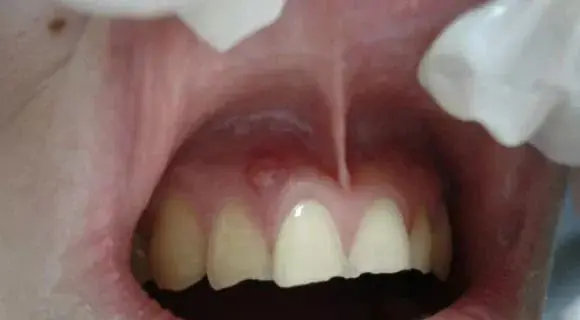

只是个小包包吗?其实并没那么简单!你看到的只是表面现象,长脓包说明牙龈内的牙根已经发炎,细菌感染牙髓演变成牙根炎症,引起牙槽骨蔓延,牙槽骨遭到炎症影响,所以牙龈上才会鼓起一个脓包,从根尖到牙根的瘘管,脓包内产生的分泌物由此流出。而出现这种问题就必须去看牙医了,否则情况就会越来越严重。

当蛀牙蛀到牙髓的时候,细菌感染了牙髓后逐渐繁殖,炎症通过牙髓进而发展大牙根、牙槽骨然后再开始慢慢蔓延,牙槽骨遭到破坏,吸收,便会在牙龈上鼓起一个脓包,形成从根尖到牙根的瘘管,炎症产生的分泌物便由此流出。